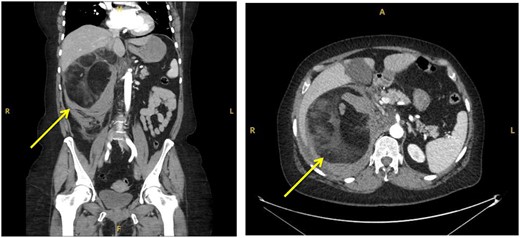

The patient was subsequently transferred over to the local specialty Urology Centre. Here the patient became tachycardic and required supplemental oxygen. A suspicion of increasing blood loss or a pulmonary embolism (PE) was raised. A repeat CTAP in arterial and venous phases along with a CT pulmonary angiography (CTPA) was conducted. The CTAP again showed a large right-sided retroperitoneal mass, now described as mixed fat and soft tissue densities characteristic of AML. The surrounding retroperitoneal bleeding was thought to have increased in size, indicating likely active haemorrhage (Fig. 2). CTPA showed no PE.

Sequential transverse sections of CTAP in arterial phase showing extent of lesion down to level of right Ilium bone.